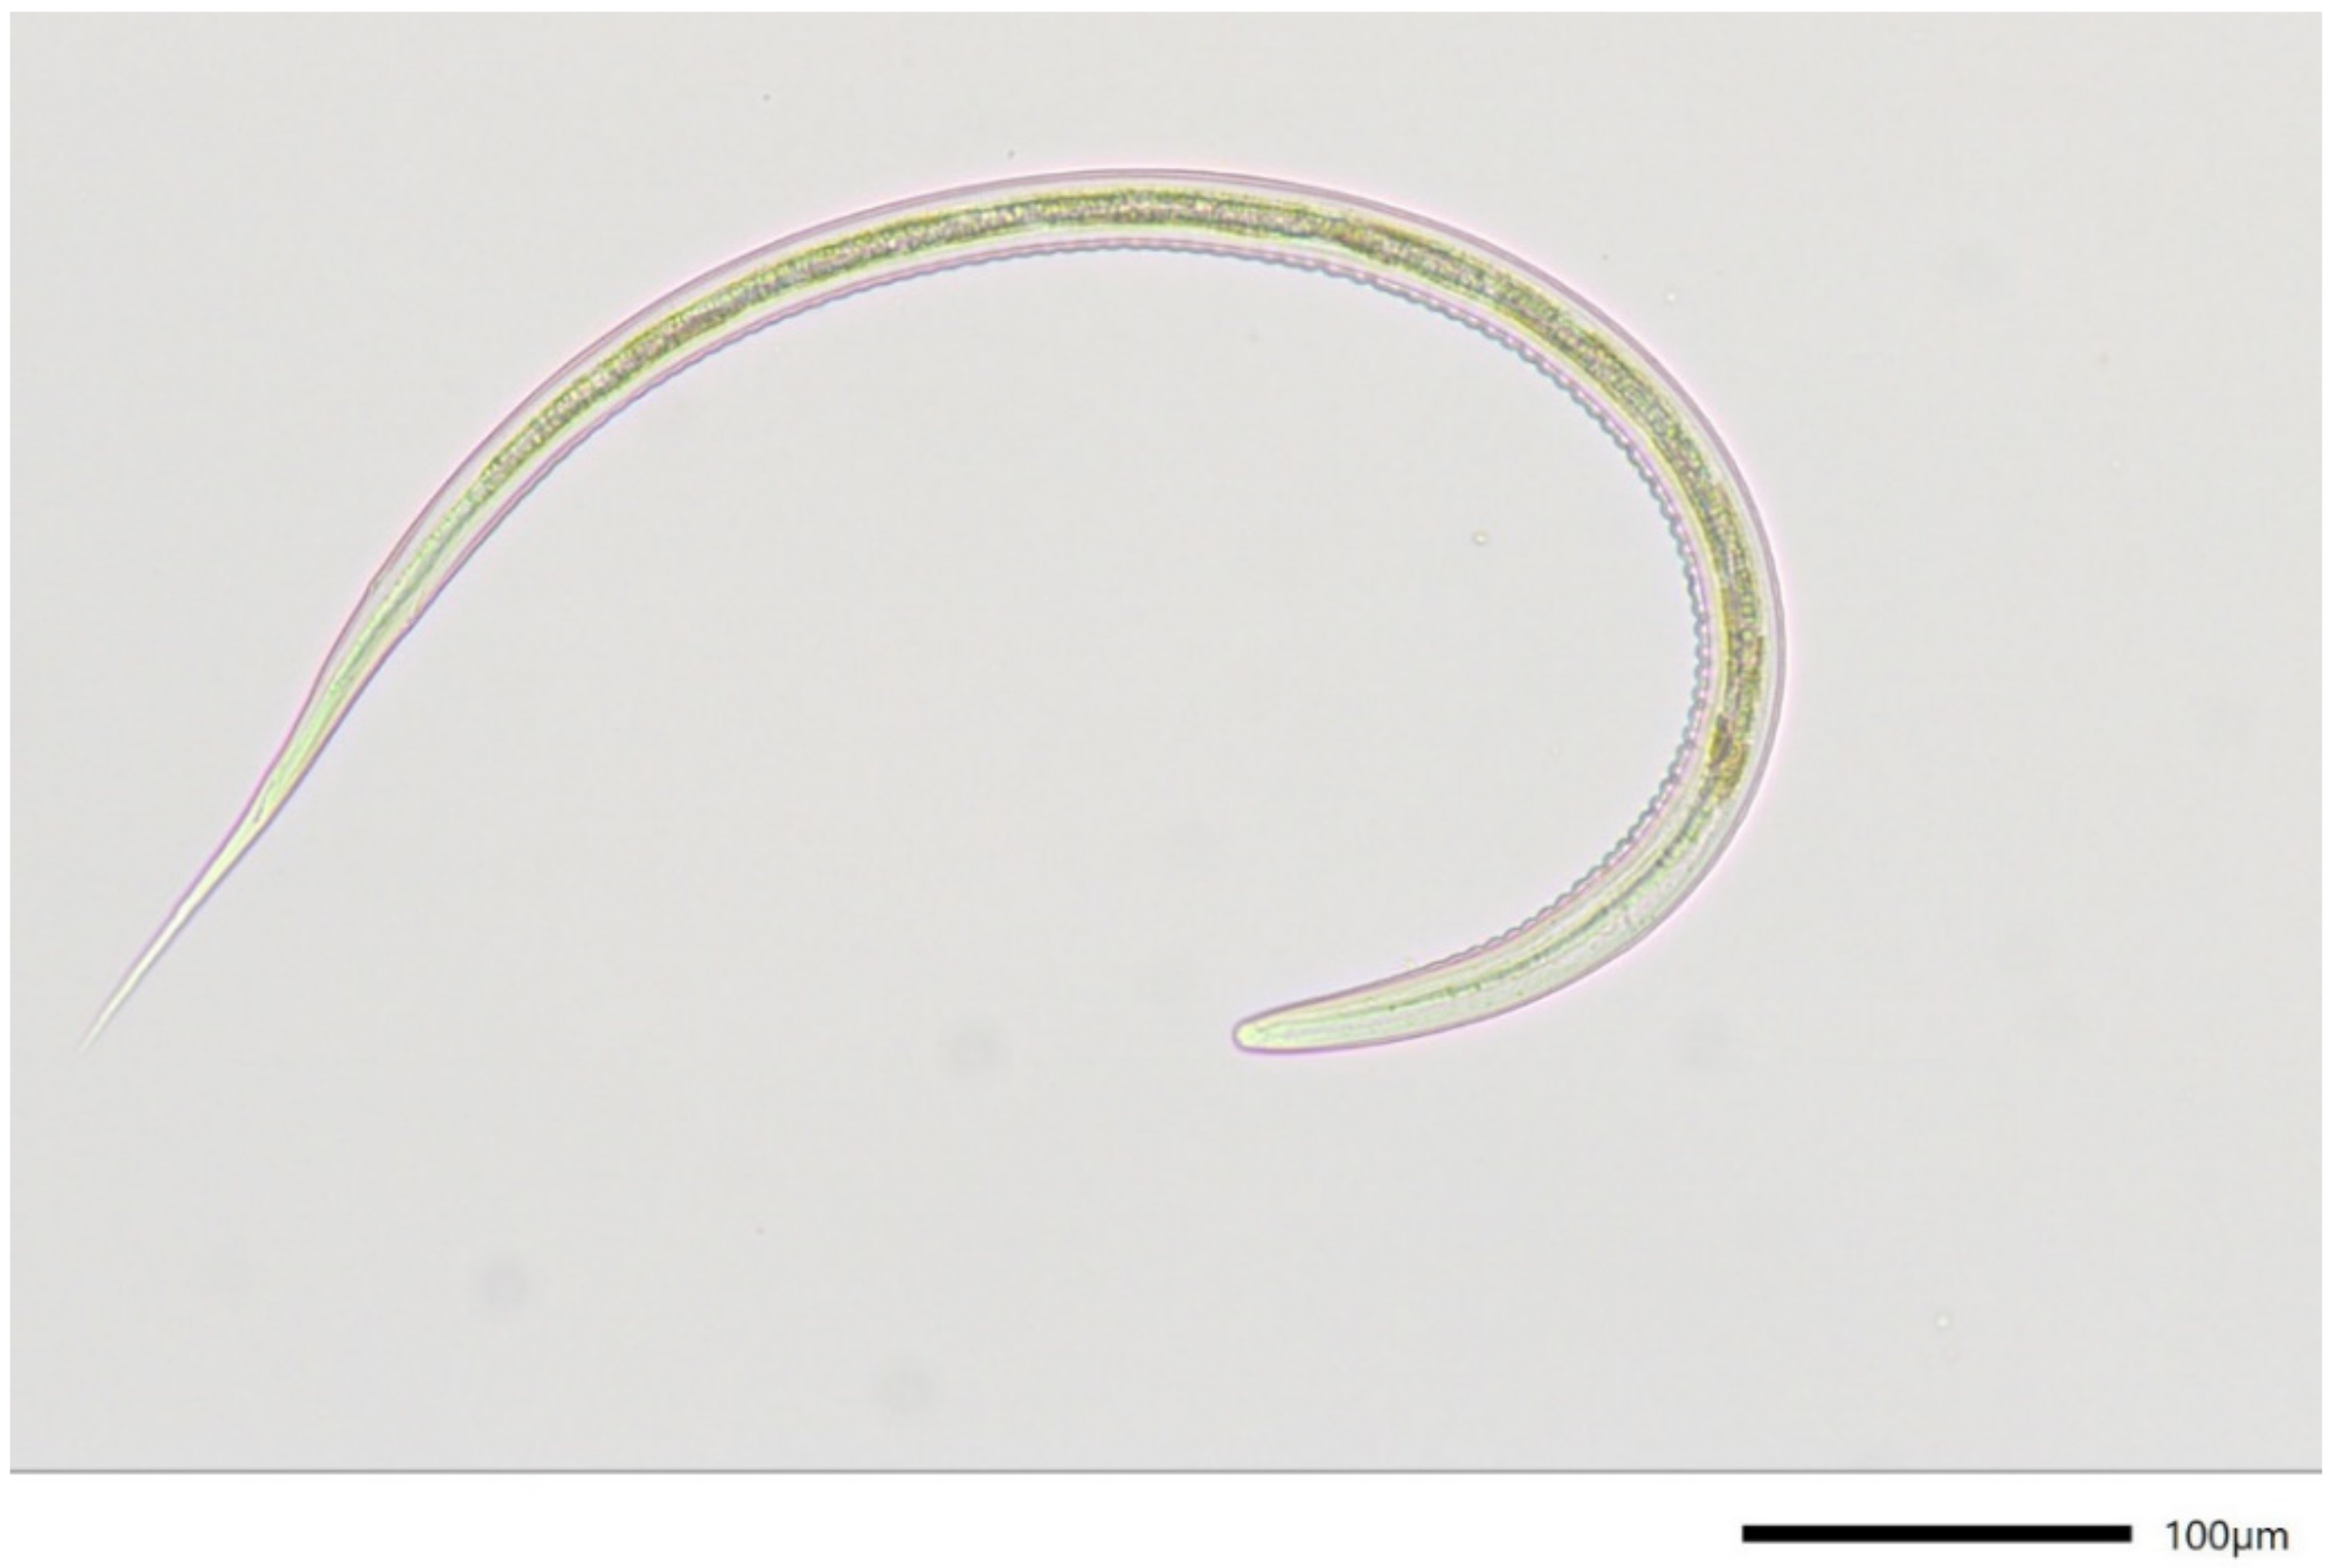

- Van Wyk, J.A.; Mayhew, E. Morphological identification of parasitic nematode infective larvae of small ruminants and cattle: A practical lab guide. Onderstepoort J. Vet. Res. 2013, 80, 539. [Google Scholar] [CrossRef] [PubMed]